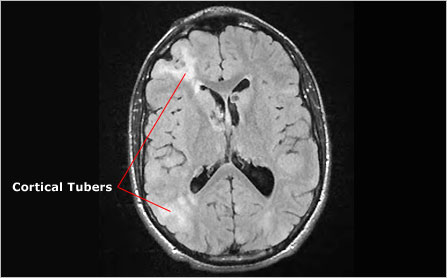

Cortical Tuber

A cortical tuber is a region of the brain that develops abnormally. These lesions are benign tissue growths that displace normal tissue growth possibly contributing to neurological problems such as seizures, and learning and behavioral issues. Tuberous sclerosis complex is named after these growths. Also known as tuber.